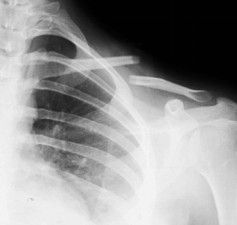

Большинство переломов могут быть диагностированы с помощью простых антеропостериальных рентгенограмм. Рентгенограммы наклона головки 20 ° устраняют влияние перекрывающихся грудных полостей. Пациенты должны быть рентгенограмма в положении самоподдерживания, чтобы лучше визуализировать смещение переломов. Веса для рентгенограммы помогает в оценке целостности ростральной клавикулярной связки в дистальной ключице или акромиоклавикулярной повреждениях суставов. Взятие рентгенограммы грудной клетки помогает исключить связанную торакальную травму, а укорочение может быть оценено путем сравнения с контралатеральной ключицей, а также исключая лопатологическую стенку.